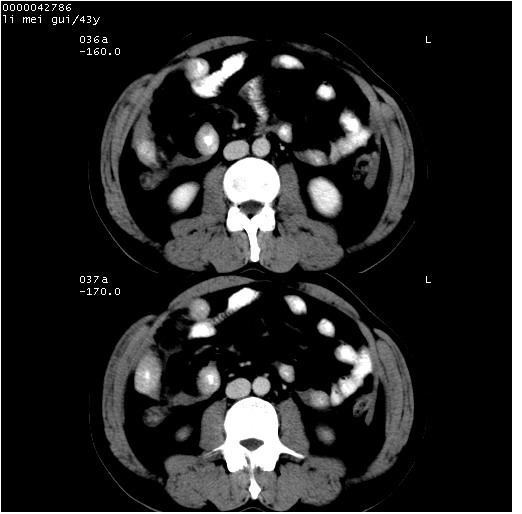

| 患者,男,43岁。突发腹痛2小时,面色苍白,难以平卧。自述近期无明确外伤史,为摩托车驾驶员。 腹部b超检查:脾脏中上极回声异常,肿瘤待排。 临床诊断:腹痛原因待查。 上中腹部ct轴位平扫+增强扫描(层厚10mm,螺距1.0,重建间隔10mm),图像如下: ![]() ![]() ![]() ![]() ![]() ![]() ![]() ![]() ![]() ![]() ![]() ![]() ![]() ![]() ![]() ![]() ![]() ![]() ![]() ![]() ![]() ![]() ![]() ![]() ![]() ![]() ![]() ![]() ![]() ![]() ![]() ![]() ![]() ![]() ![]() zrs发言:支持脾破裂 wwp发言:支持脾破裂并腹水。 xulianj发言:脾脏肿瘤破裂可能性大 zsl6918发言:不像肿瘤出血,考虑还是与外伤后引起的慢性出血有关 zzyy发言:平扫见肝周及脾周积液,脾内密度不均。脾内肿瘤较少见。还是外伤性脾破裂。 沈丘东方医院发言:脾门区一个不均匀强化病灶与其周液体相连多考虑脾占位破裂出血 yixianman001011发言:脾破裂并腹水是可以肯定的,具体原因多以肿瘤性破裂出血,脾脏淋巴瘤可能性大. 结果: 术后,经详细询问患者,其仔细回忆:一月前骑摩托时左侧腰部与别人有“轻微”触碰,因责任在自已,当时又无明显不适,未引起注意。 临床术后诊断:脾破裂并失血性休克(1.外伤性迟发性脾破裂。2.脾脏肿瘤破裂?) 术后标本病检:脾破裂并出血,未见明显肿瘤成份。 原贴地址:http://www.radinet.com.cn/forum_view.asp?forum_id=4&view_id=34070 |